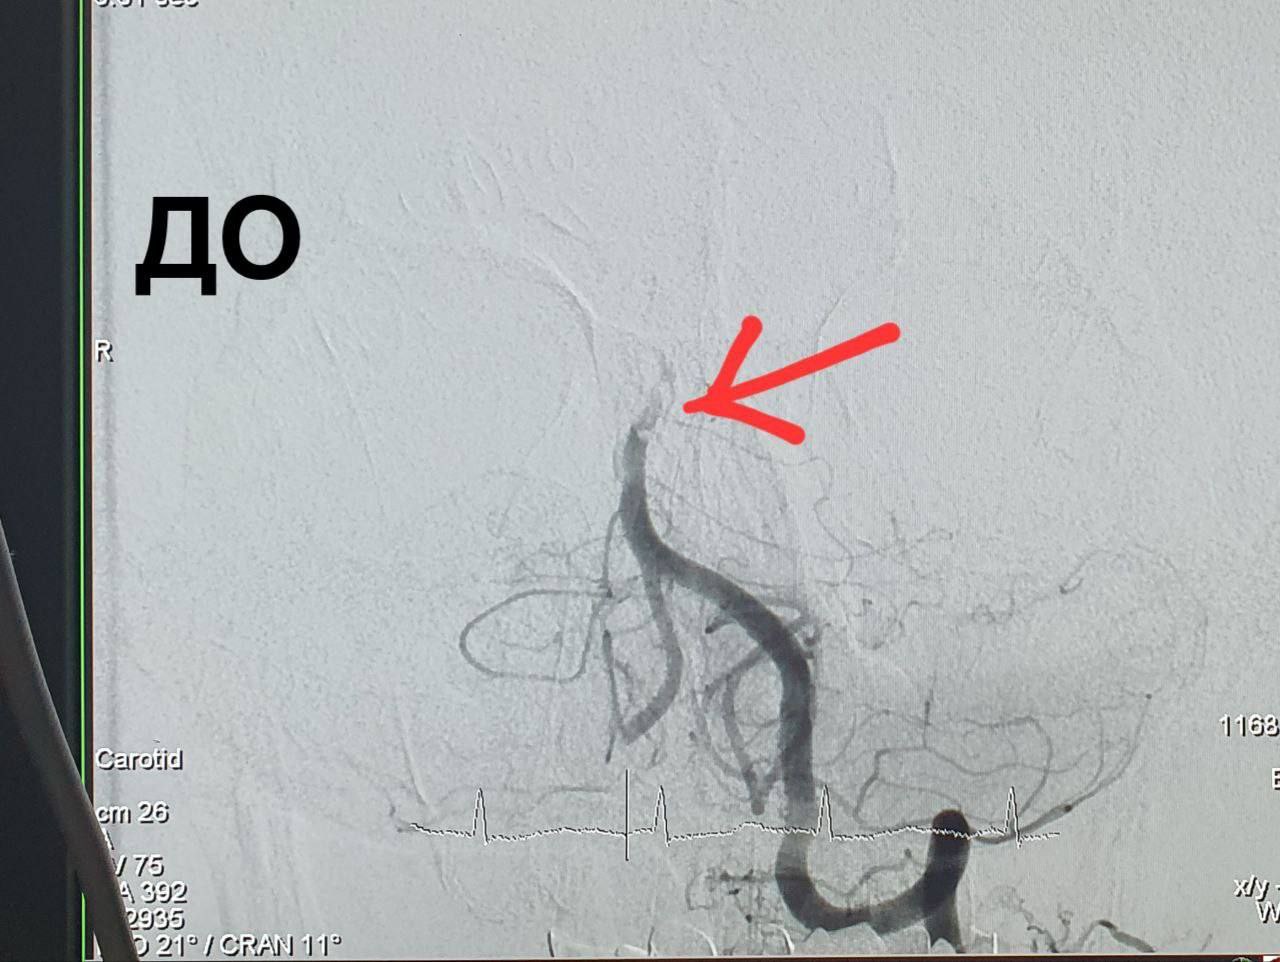

В Оренбурге рентген-хирурги Алексей Демин и Эдуард Гаврилов удалили 59-летнему пациенту тромб в базилярной артерии мозга.

Сначала пациент был доставлен в больницу имени Пирогова. Там ему сделали компьютерную томографию головного мозга и нашли закупорку в базилярной артерии.

Из артерии хирурги извлекли большое количество тромбов и полностью восстановили её проходимость.